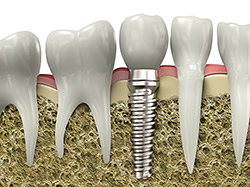

Dental implants are small titanium rods surgically implanted into your jawbone to replace missing teeth. As you heal from the surgery, the rods fuse to your bone and form a strong and sturdy root, which looks and feels like a natural tooth. When the implant is ready to be restored with a crown or bridge, it will feel natural to bite, chew and speak. The power behind dental implants is that they help to prevent bone loss in your jaw. If you have lost a tooth, the bone beneath it will slowly begin to shrink through the process of resorption. This can cause your face to appear sunken in, cause the lips to look thinner and more wrinkled, cause your cheeks to have a more hollow appearance, and make it very difficult to have replacement teeth placed in the future. However, when you have an implant placed in your jaw at Ash & Rowan Family Dentistry, it helps prevent bone loss by replacing the tooth roots that your natural teeth had before.

Dental implants are an excellent option to replace missing teeth because, unlike other tooth replacement options, they protect your healthy jawbone and prevent further bone loss in the jaw. Different types of tooth replacements, like bridges or dentures, only replace the visible part of the tooth above the gum line, but they do not prevent bone loss and can lead to changes in facial features over time. Because dental implants replace the whole tooth, they are a long-term solution for restoring your smile. They look and feel natural, require no special care outside of regular brushing and flossing, and can last a lifetime when properly cared for. Plus, with dental implants, you regain the full function of your teeth so you can eat and speak normally again. This positively affects your oral and overall health, self-image, and emotional well-being.